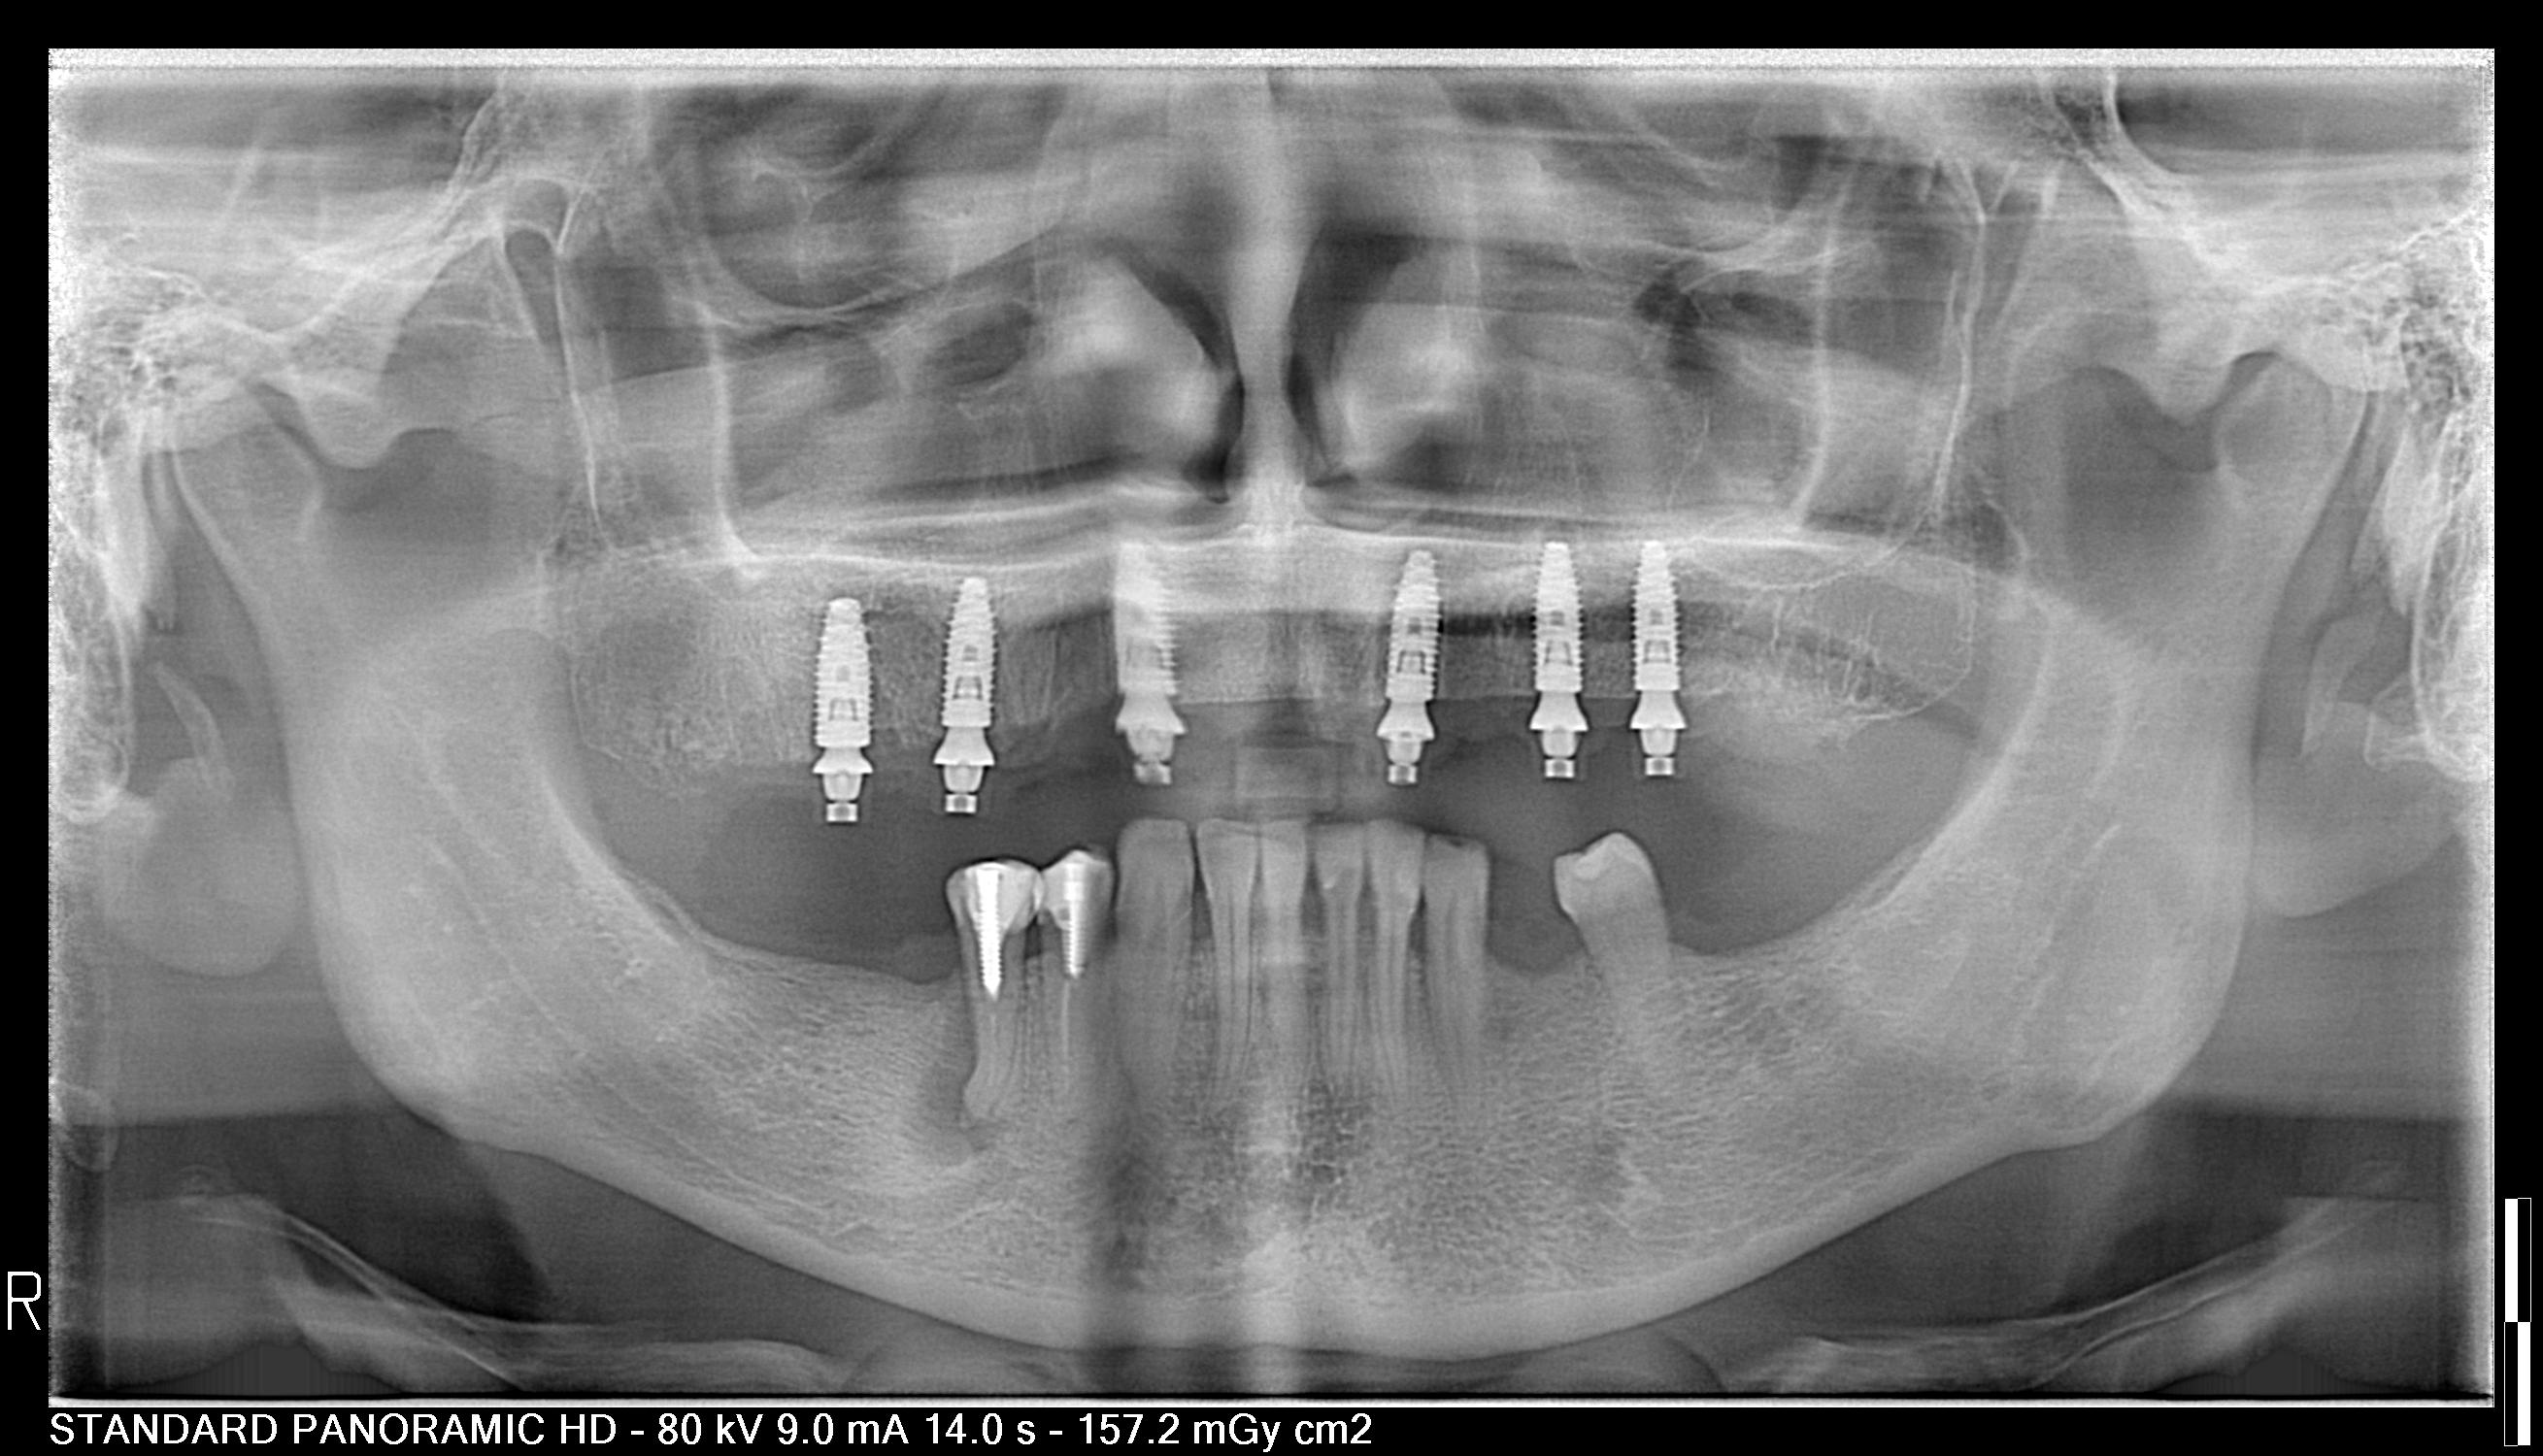

Ատամներ մեկ օրում, նաև հայտնի որպես ատամնային իմպլանտներ մեկ օրում կամ էքսպրես իմպլանտացիա, ստոմատոլոգիական հեղափոխական մեթոդ է, որը թույլ է տալիս Այցելուներին մեկ օրում ունենալ անշարժ ատամնաշար : Այո՛, այս ամենը կարող է տեղի ունենալ ընդամենը 24 ժամվա ընթացքում, այլ ոչ թե բոլորիս հայտնի 5-6 ամսվա ընթացքում։

Այս ծառայությունը Երևանում մատուցելու հիմնական մեթոդներից մեկը All-on-4 մեկ օրում մեթոդն է: Այն աշխատում է ատամնային կամուրջների կառուցվածքի նման. այս մեթոդի դեպքում նոր ատամնաշարը ամրանում է 4 հիմնական հենարանների՝ իմպլանտների վրա, որոնք ապահովում են ամբողջական կայունություն:Ովքե՞ր են հարմար թեկնածուները